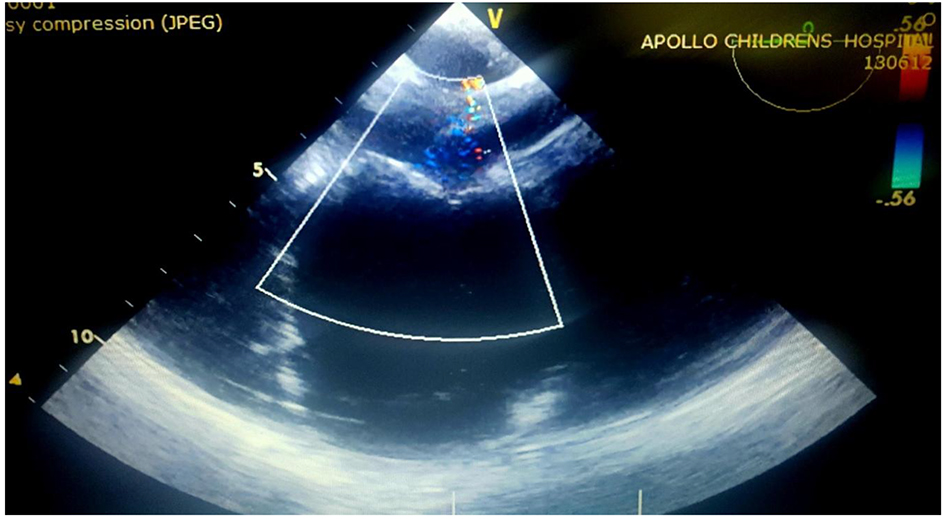

A 15-year-old girl presented with history of high-grade fever of 2 - 3 days duration, and refractory generalized tonic clonic seizures with altered sensorium (status epilepticus) of 3 - 4 h duration prior to presentation in pediatric emergency. The patient had no past history of head trauma, abnormal movements or behavior, headache, visual disturbances, ear discharge, drug intake, insect bite, breathlessness on excretion, palpitations, edema, sore throat, joint pains, skin rashes, bleeding, and menorrhagia. Patient was developmentally normal going good in her school grades, belonging to upper middle class, and resides in urban locality. No significant similar family history was noted. On examination at admission, patient was in altered sensorium with intermittent tonic posturing, no rashes, active bleeding, injury or inset bite marks, pallor, icterus, cyanosis, lymphadenopathy, and edema present. Patient was febrile with temperature of 102 °F (38.9 °C), pulse rate was 110/min, regular, good volume, and blood pressure was 120/70 mm Hg in right upper limb. Neurological examination showed altered sensorium not responding to commands or painful stimulus (Glasgow coma scale (GCS) score was < 8). There was no cranial nerve involvement, tone increased in all limbs, deep tendon reflexes brisk (3+), no neck rigidity, bilaterally normal sized pupils and normal reaction to light. Respiratory system bilateral normal vesicular breath sounds were heard with equal air entry. Cardiovascular system examination S1-S2 heard no added sounds. On abdominal examination, no organomegaly appreciated. With these findings, patient was diagnosed to have encephalitis probably of viral etiology. Seizures were controlled with antiepileptic drugs and in view of low GCS score (< 8), patient was intubated and was put on mechanical ventilation in critical care unit. In critical care unit, she had an episode of fluctuating blood pressure measurements with hypotension (< 50th percentile for age and height) requiring inotropic support. Lab findings were normal with complete blood count showing Hb of 11 mg/dL, TLC of 8,500, platelets of 345,000/µL except for erythrocyte sedimentation rate (ESR) which was high (70 mm/h), liver function test showed normal bilirubin levels and other parameters, normal renal function test, normal electrolytes and blood sugar level. Viral serology for Japanese encephalitis (JE), PCR for herpes simplex virus (HSV) and blood culture sensitivity were sent. Echocardiography was done to assess ventricular function and rule out cardiac cause for hemodynamic instability. Incidentally echocardiography revealed a large mass (56 × 40 mm) in the left atrium attached to lower part of interatrial septum which was of homogenous echogenicity, pedunculated, non-cystic, with no calcific focus (Fig. 1a, b). The mass was impinging on the mitral valve causing severe mitral stenosis (mean inflow gradient of 12 mm Hg) and moderate mitral regurgitation (Figs. 2 and 3). There was severe pulmonary arterial hypertension (estimated right ventricular systolic pressure of 60 mm Hg). Computed tomographic (CT) angiography of brain showed microinfarcts in frontal and parietal cortex. Systemic thromboembolic phenomena due to the left heart myxoma were considered and the patient was started on intravenous heparin infusion. After an informed consent, an emergency surgical excision of mass was done through midline sternotomy on cardiopulmonary bypass through right atrial approach (Fig. 4). Postoperative echocardiography confirmed complete excision of the mass. There was only mild mitral regurgitation and no evidence of residual mitral inflow obstruction (Fig. 5). Postoperative period was uneventful. Viral markers and blood culture revealed no significant growth. Mechanical ventilation, neuroprotective care and passive physiotherapy were continued for 72 h postoperatively due to low GCS. Aspirin and low molecular weight heparin were given. She was extubated on the fourth postoperative day when the sensorium improved. Subsequently, she was noticed to have mild left-sided hemiparesis. She was discharged on the seventh postoperative day on aspirin. Patient completely recovered from the neurological deficit at 1 month of postoperative period. Excised mass was gray to red in color, gelatinous, mucoid, soft and friable with irregular margins and hemorrhagic spots suggesting myxoma (Fig. 6). Histopathology examination of the mass showed myxomatous matrix containing stellate and fusiform myxoma cells confirming the diagnosis of atrial myxoma (Fig. 7). During follow-up at 1-year postoperative period, she was neurologically normal and hemodynamically stable with no regrowth of cardiac myxoma. Aspirin was stopped and yearly follow-up was advised to monitor for recurrence of myxoma.

![]() Click for large image | Figure 2. Echocardiography color Doppler showing moderate mitral regurgitation. |